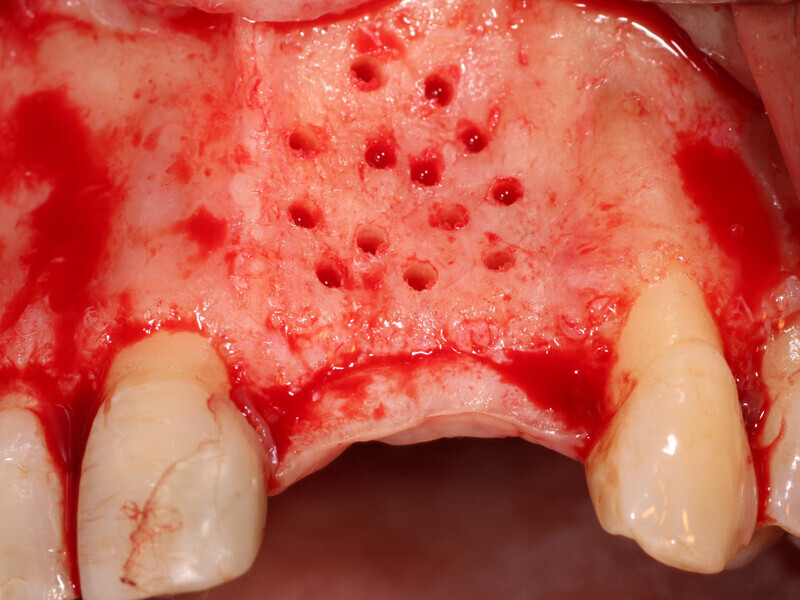

Fig. 4: The facial plate is fenestrated with a bur through the cortical bone in the edentulous space that will receive the osseous graft.